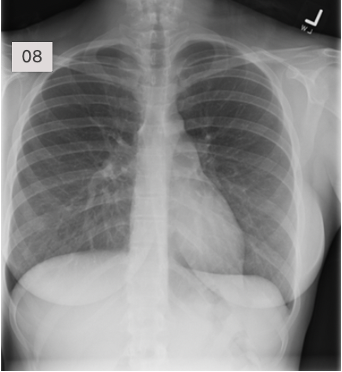

In a good CXR, what 2 criteria can tell if penetration is adequate?

A

• The left hemidiaphragm should be visible to the edge of the spine

• The vertebrae should be visible behind the heart